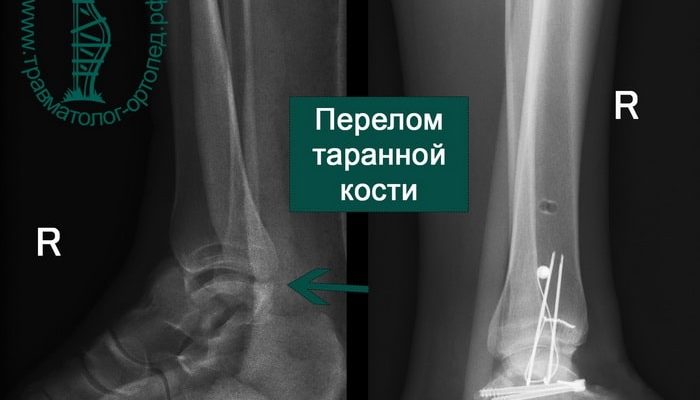

таранной кости

Анатомия Таранной Кости: Всё, что Нужно Знать о Незаменимом Элементе Стопы Когда мы задумываемся о здоровье наших ног, обычно обращаем внимание на такие

Анатомия суставных поверхностей таранной кости: все, что нужно знать о структуре и функциях Когда речь заходит о строении стопы и её двигательной функции